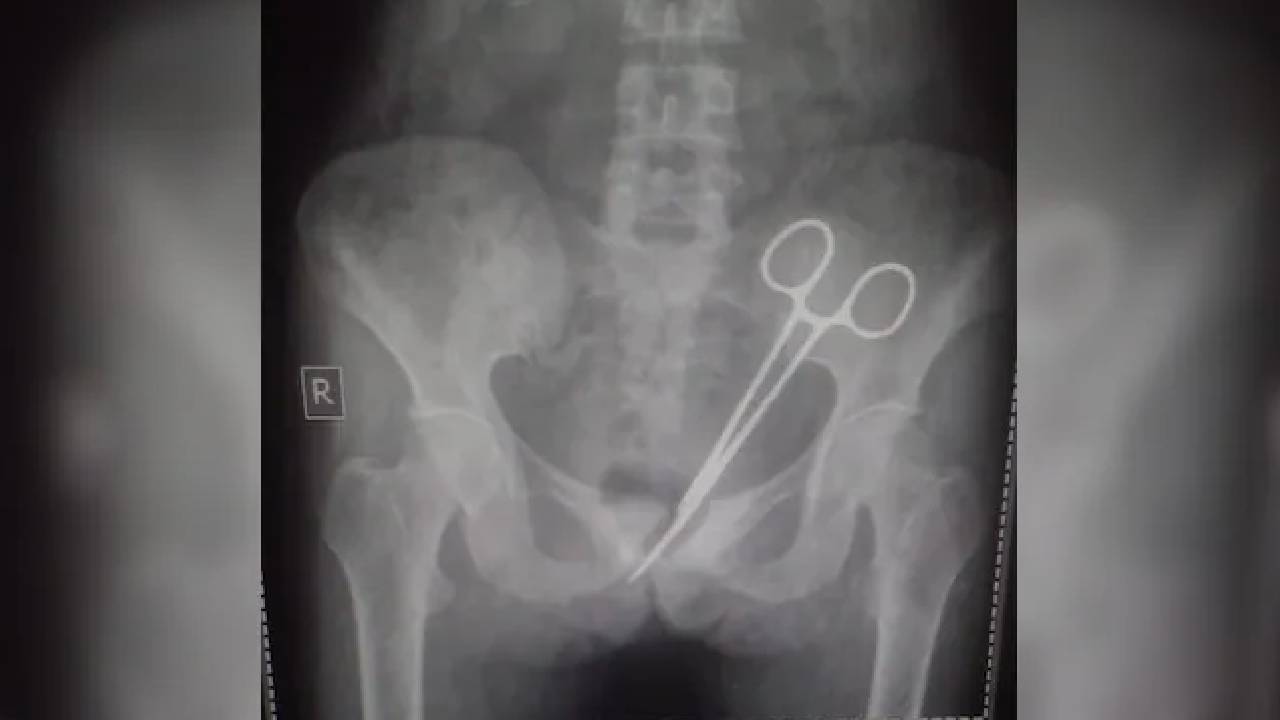

Scissors In Abdomen: సిక్కిం రాష్ట్రానికి చెందిన ఓ మహిళ కడుపులో కత్తెర, 12 ఏళ్ల తర్వాత బయటపడింది. అపెండిక్స్ ఆపరేషన్ నిర్వహించే సమయంలో నిర్లక్ష్యంగా వ్యవహరించిన వైద్యులు కత్తెరను మహిళ పొత్తికడుపులోనే వదిలేశారు. ఆమె గత దశాబ్ధకాలంగా నొప్పితో బాధపడుతూనే ఉంది. చాలా మంది వైద్యుల్ని సంప్రదించినప్పటికీ, నొప్పి తగ్గలేదు. చివరకు ఈ నెల ప్రారంభంలో ఆమె కడుపులో కత్తెర ఉన్నట్లు వైద్యులు నిర్ధారించారు.

45 ఏళ్ల మహిళ శరీరంలో సర్జికల్ కత్తెరని గుర్తించారు. 2012లో ఆమెకు అపెండిసైటిస్ ఆపరేషన్ చేసిన వైద్యులు కత్తెరని వదిలేశారు. 2012లో గాంగ్‌టక్‌లోని సర్ థుటోబ్ నామ్‌గ్యాల్ మోమరియల్ ఆస్పత్రిలో ఆపరేషన్ జరిగినట్లు ఆమె తెలిపింది. అప్పటి నుంచి నొప్పితో బాధపడుతూనే ఉన్నానని, ఎంతో మంది వైద్యుల్ని సంప్రదించినప్పటికీ మందులు ఇచ్చారని, కానీ నొప్పి మాత్రం తగ్గలేదని చెప్పారు.

అక్టోబర్ 08న మళ్లీ అదే ఆస్పత్రిక వెళ్తే, ఎక్స్-రేలో సర్జికల్ కత్తెర బయటపడింది. వైద్యులు వెంటనే ఆపరేషన్ నిర్వహించి కత్తెరని బయటకు తీశారు. ఆమె ప్రస్తుతం కోలుకుంటోందని వైద్యులు వెల్లడించారు. ఈ వార్త వైరల్ కావడంతో ఆస్పత్రిపై ప్రజలు ఆగ్రహం వ్యక్తం చేశారు. అధికారులు దీనిపై దర్యాప్తు చేస్తున్నారు.